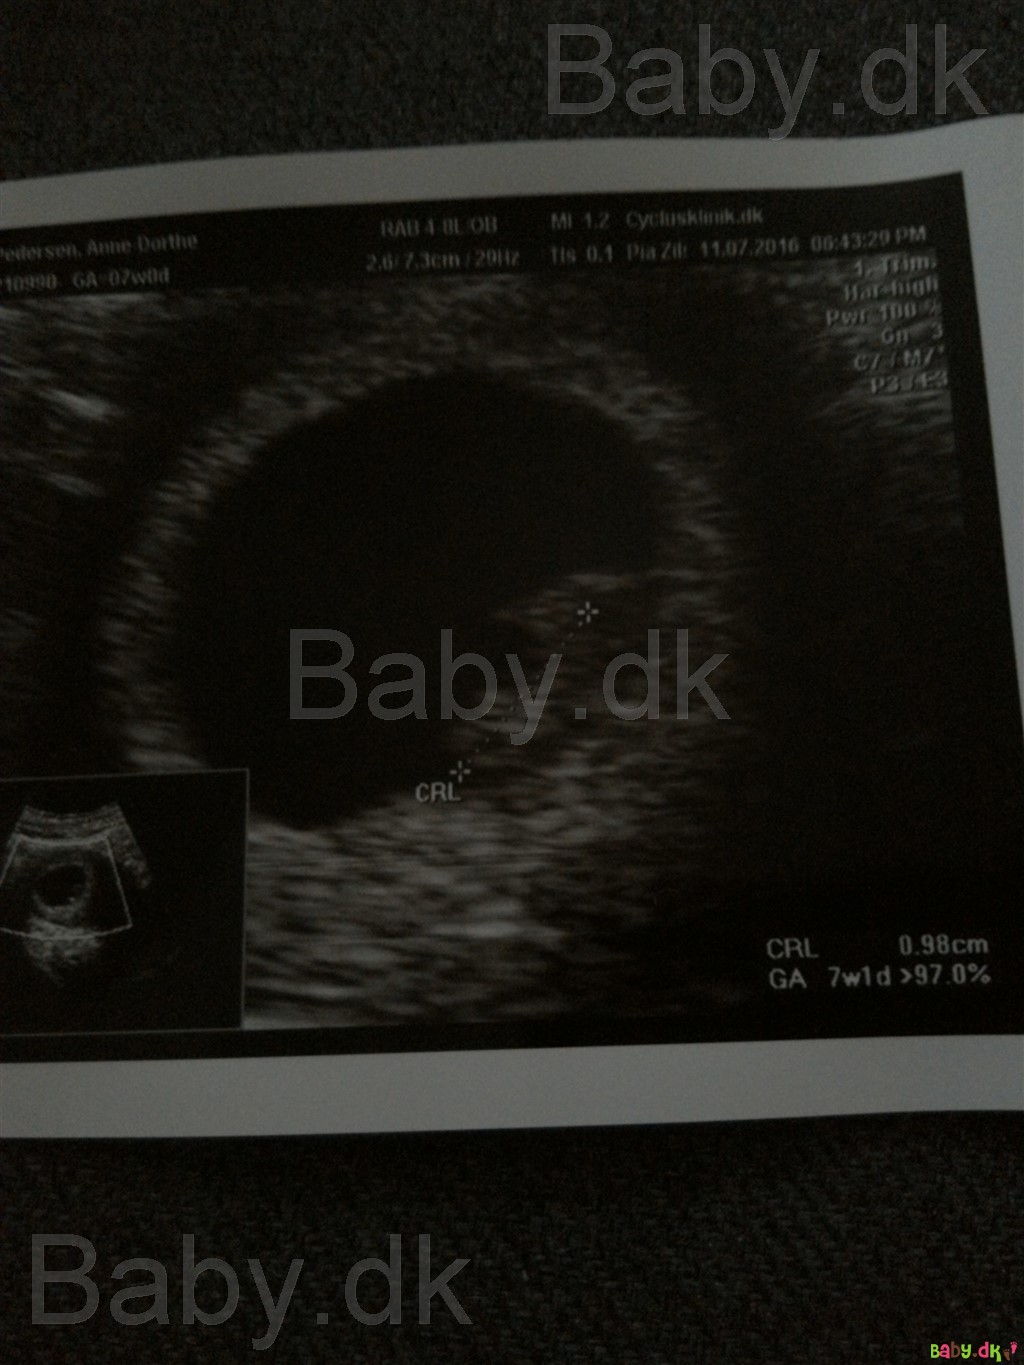

Så har jeg været til scanning og så den fineste lille spire med det fineste hjerteblink

Alt så perfekt ud og blødningen kunne ikke engang ses så den kom fra livmoderhalsen

Alt efter hvordan hun målte Baby var jeg mellem 6+6 og 7+1 så det passer perfekt